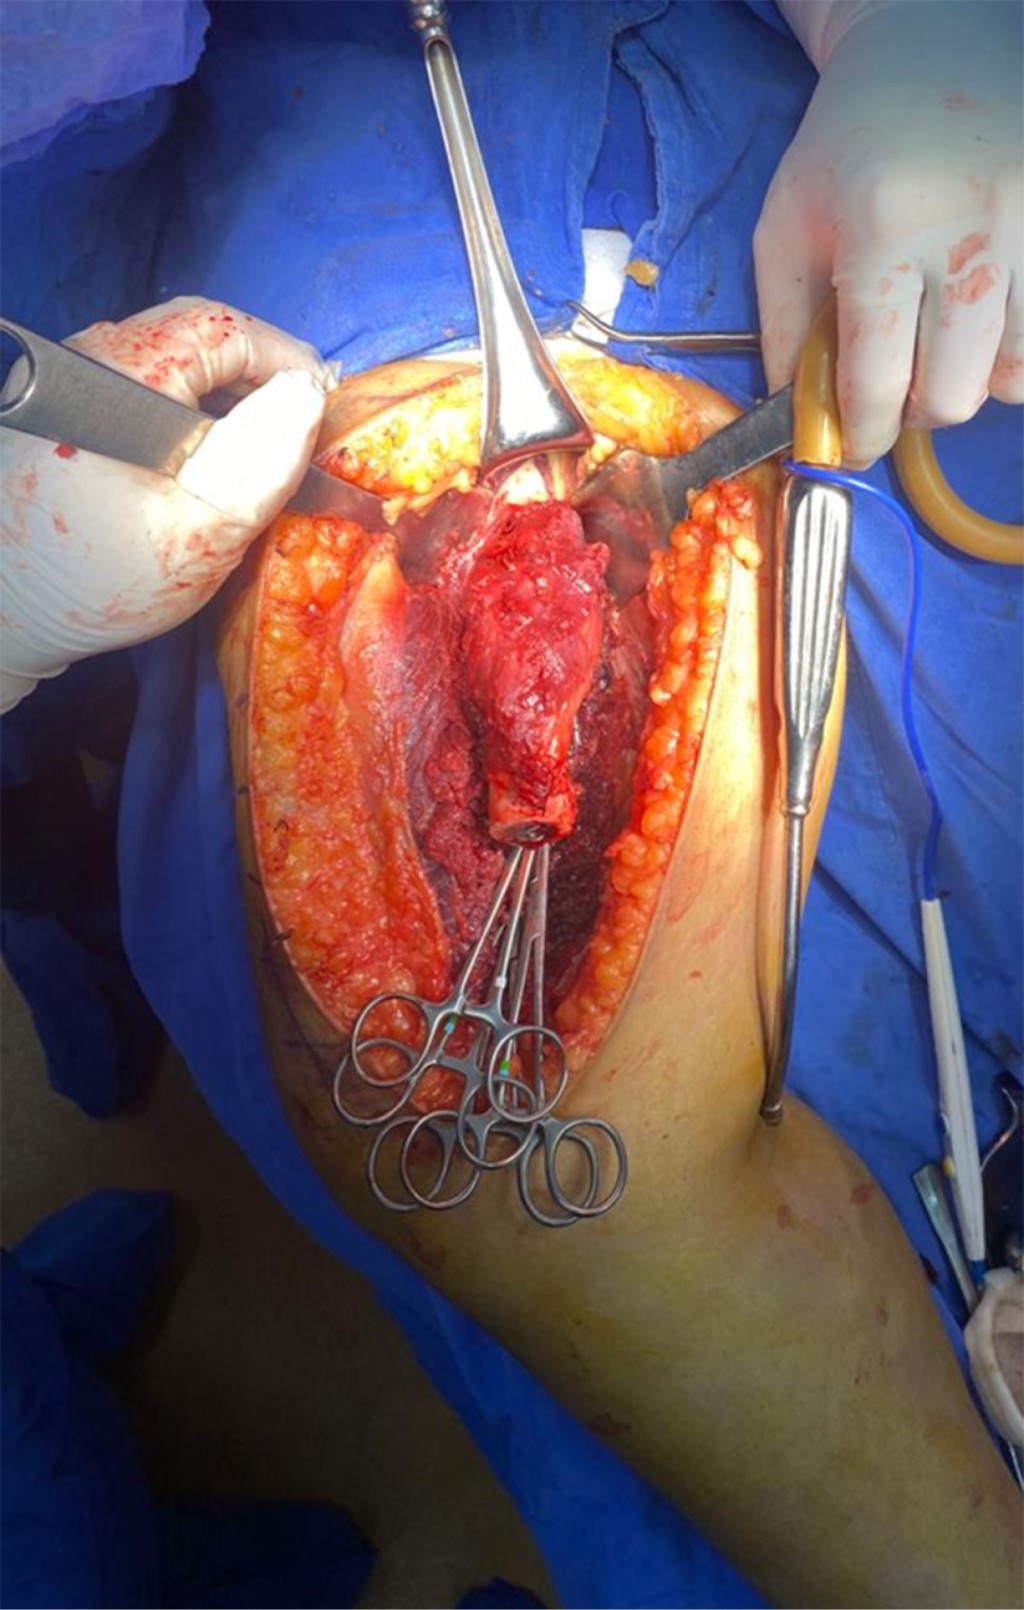

Con la paciente bajo anestesia general y en decúbito supino, se realiza asepsia, antisepsia y colocación de campos quirúrgicos estériles. Se opta por un abordaje anteromedial de fémur, mediante incisión longitudinal de aproximadamente 25 cm, disecando por planos hasta encontrar intervalo entre músculos recto femoral y vasto medial; después se encuentra el vasto intermedio, el cual se diseca hasta encontrar diáfisis femoral. Se observa tumoración en tercio medio de diáfisis femoral de aproximadamente 13 cm de longitud por 3 cm de ancho, el cual se reseca con bordes amplios, realizando osteotomía a 16 cm proximales de superficie articular de la rodilla (Figura 3); se envía muestra medular transquirúrgica, recibiendo confirmación de presencia de bordes libres por el Servicio de Patología. Se realiza segunda osteotomía a 16 cm distales del trocánter mayor, se envía segunda muestra de médula ósea, recibiendo reporte negativo para células malignas. Se realiza rimado de fémur proximal y distal con rimas diámetros 9, 10 y 10.5 hasta atravesar fosa digital proximalmente; se coloca asentador para hueso, regularizando el límite de la osteotomía. Se introduce clavo endomedular hasta limite distal establecido (Figuras 4 y 5) y se coloca prótesis diafisaria (Figura 6) con asentadores y coronas en extremos diafisarios, respectivamente. Se procede a colocar pernos de bloqueo, verificándose longitud de extremidad (Figura 7) comparando con la contralateral. Se repara intervalo entre recto femoral y vasto medial y se procede a cierre por planos.

Figura 3